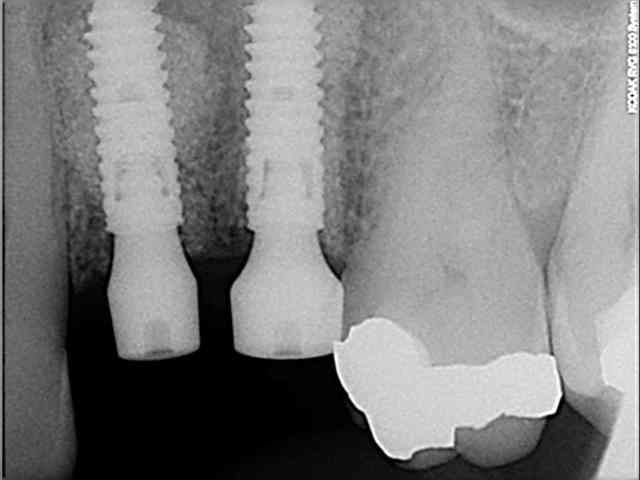

tiens voici des photos de ce matin...

patient avec kyste +++ aux apex et fenestration

je n'implante pas

je comble au Graftec

je met une membrane

je referme

8 mois après,

je vais implanter

comme je suis curieux, j'ouvre large et je regarde;

c'est décevant,le volume est là mais l'os n'est pas génial.

voilà pour les photos...

pendant que je forais, et le patient le sentait également, je sentais et entendais les particules de graftec.

en plus au bout de 8 mois j'aurai espéré trouver quelque chose de mieux non ?